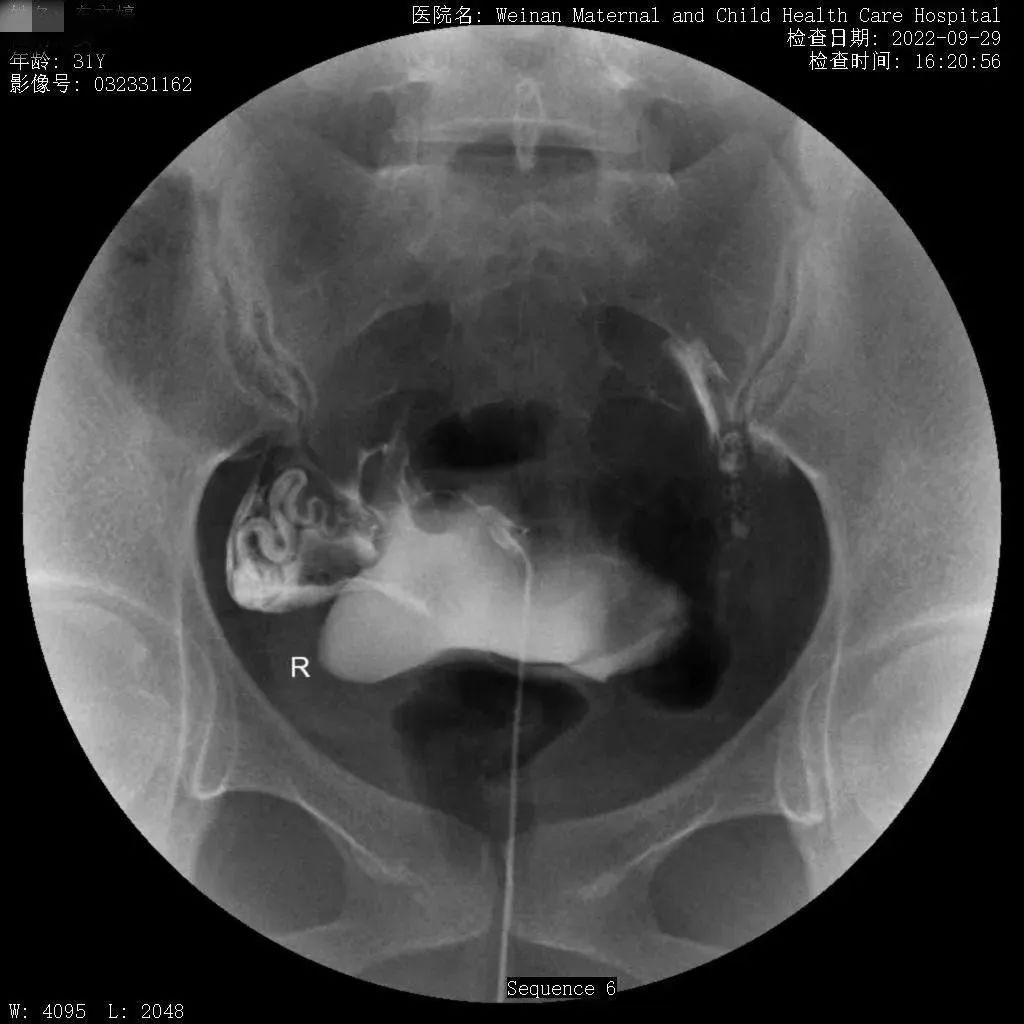

为满足临床需求,除开展传统X线检查外,近年又相继开展了静脉肾盂造影、“T”型管造影及子宫输卵管造影等多种造影检查、乳腺钼靶成像、遥控灌肠治疗小儿肠套叠等较前沿的X线检查。尤其是治疗小儿肠套叠,现已治愈几百余例患儿,遥控灌肠整复仪治疗小儿肠套叠具有安全、迅速、高效的特点,避免了患儿手术,减轻了家庭经济负担。

不育不孕症的子宫输卵管造影检查